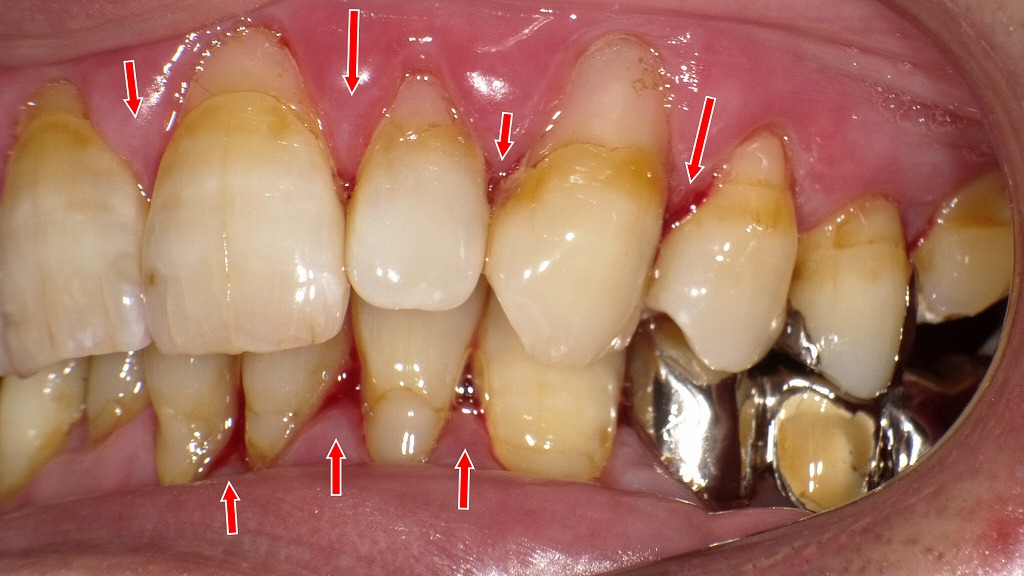

磨き残しチェック:染め出しで見える歯周炎のリスク部位

この写真は、歯の表面に残ったプラーク(歯垢)を染め出した状態を示しています。染め出し液によって赤〜ピンク色に染まっている部分が、**磨き残しのある細菌の塊(バイオフィルム)**です。

赤く染まった部分はプラーク(細菌の塊)で、磨き残しが集中している部位です。

炎症や出血が起きていた場所と染色部位が一致しており、歯周病の進行原因が明確に示されています。① 歯肉縁上に広くプラークが付着

前歯部・犬歯部を中心に、歯と歯ぐきの境目が濃く染まっています。

この部分の磨き残しは**歯肉の炎症(腫れ・出血)**をもっとも引き起こしやすい部位です。② 歯間部に強い染まり:歯間清掃不足の所見

歯と歯の間が特に強く染まっており、

- フロス

- 歯間ブラシ

が十分に使えていない状態が反映されています。

歯間部の磨き残しは、縁下歯石の形成や歯周ポケットの悪化につながりやすい場所です。③ 糖尿病患者に特徴的な炎症の強さと一致

もともと腫れ・出血が確認されていた部位と、今回濃染されている部位が一致しており、

プラークの付着が歯周炎をさらに悪化させていることが明確に示されています。糖尿病があると、同じ量のプラークであっても

- 炎症が強く出る

- 出血しやすい

- 歯周病が進行しやすい

という特徴があるため、この染め出し結果は病態をよく反映しています。

④ 下顎前歯部:特にプラークが厚く付着

下顎前歯の裏側〜歯肉との境界は、唾液腺の影響で歯石がつきやすい場所でもあり、今回も強く染まっています。

この部位の清掃改善は、治療効果に直結します。歯磨き指導と歯石除去後で歯ぐきの炎症が大きく改善